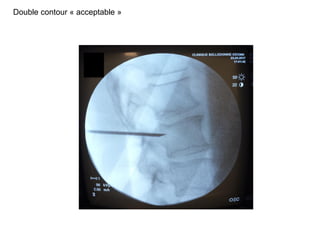

Double contour

Positionnement de l’ampli

clichés de profil

Double contour « acceptable »